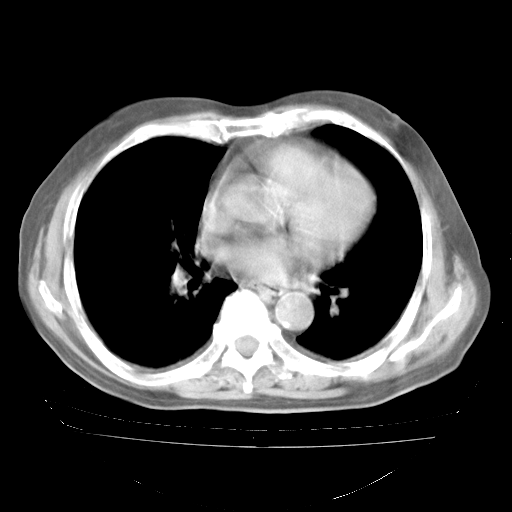

今天部分检查

轻微咳嗽,无痰,(体温正常时)R20次/分,P75次/分,双肺底、腋下可闻及少量捻发音。下肢轻度浮肿。

血常规:白细胞9.11×109/L,N0.92,L5.64,血小板39.2×109/L,HB148g/L,ESR2mm/H。

尿常规:潜血+

血生化:总蛋白69.71g/L,白蛋白38.40g/L,球蛋白31.31g/L,CRP27.9mg/L,尿素氮11.98mmol/L,肌酐106μmol/L,乳酸脱氢酶1099 U/L,肌酸激酶108U/L,CK-MB 61U/L。

腹部B超:胆囊壁增厚,肝、胆、胰、脾、肾无异常,肠系膜淋巴结、腹膜后淋巴结无增大。

ECG:右心室增大

心脏超声检查:无右心室增大。

增加治疗:异烟肼、利福平、乙胺丁醇,静滴左氧氟沙星、参麦注射液。甲强龙从80mg暂减为40mg。

强的松3月1日改为10mg qd,4月1日改为10mg qod。3月份以前的减量过程和环磷酰胺疗程需等明天查看记录(我岳父自己做的记录在他家里)。